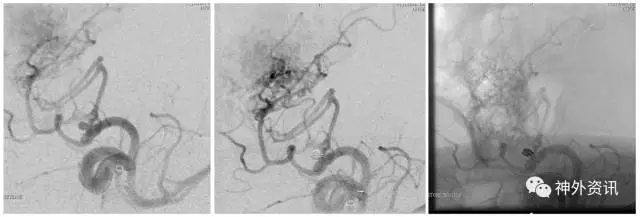

(DSA:烟雾病;左侧大脑后动脉P2段夹层动脉瘤)

(3D重建:动脉瘤形态极不规则,远/近端血管迂曲严重伴狭窄)

(左:Envoy DA导引导管-右侧椎动脉V3段;右:支架导管成功超选左侧大脑后动脉)

(支架辅助弹簧圈栓塞-动脉瘤不显影,载瘤动脉通畅)

(术后3D双容积重建)